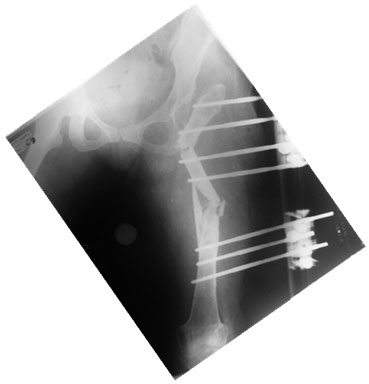

Before Removal

Both the ostetomies have healed. The distraction gap is well consolidated.